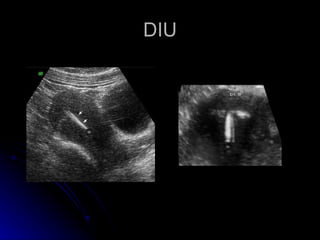

Este documento proporciona una lista de indicaciones y condiciones médicas para un ultrasonido pélvico realizado por el Dr. Napoleón Gallifa, incluyendo sangrados uterinos anormales, miomatosis, dispositivos intrauterinos, masas anexiales y seguimiento folicular, así como condiciones del útero como miomas, hiperplasia endometrial y cáncer de endometrio y ovario.